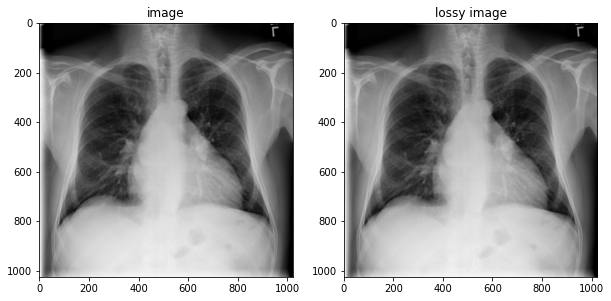

image = tfio.image.decode_dicom_image(image_bytes, dtype=tf.uint16)

lossy_image = tfio.image.decode_dicom_image(image_bytes, scale='auto', on_error='lossy', dtype=tf.uint8)

fig, axes = plt.subplots(1,2, figsize=(10,10))

axes[0].imshow(np.squeeze(image.numpy()), cmap='gray')

axes[0].set_title('image')

axes[1].imshow(np.squeeze(lossy_image.numpy()), cmap='gray')

axes[1].set_title('lossy image');